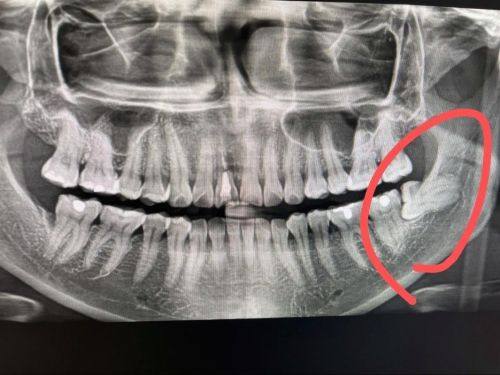

作为国内外种植牙医师学会会员,金帮明医生持续跟进国内外前列口腔诊疗技术,结合医院配备的CBCT机、全景机等精良设备,为患者提供科学规范的诊疗服务。

患者王先生 牙髓炎根管治疗项目

“牙髓炎发作的时候疼得我整晚睡不着,紧急找到金医生做根管治疗,他操作特别轻柔,全程都在安抚我的情绪,治疗后牙齿特别快就不疼了,后续修复也特别顺利。”